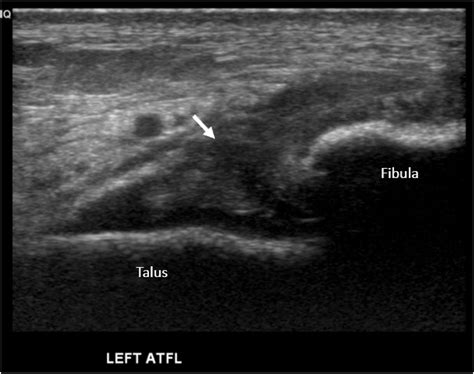

• Imaging Tests: X-rays can rule out fractures, while MRI or ultrasound can provide detailed images of the ligament to confirm the tear.